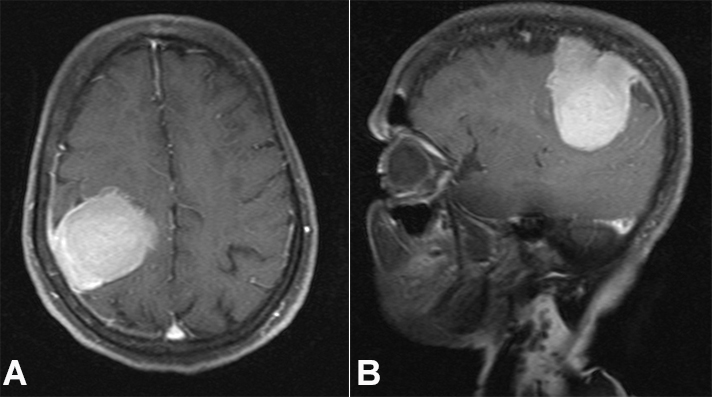

A 27-year-old previously healthy male presented with episodes of generalized tonic-clonic seizures. There was no history of headache, visual disturbances, ataxia, or paresis. The results of routine laboratory investigations, including complete blood count, blood biochemistry, urinalysis, and electrocardiogram were within normal limits. Chest X-ray and abdominal ultrasound were normal. The cranial MRI revealed an intensely enhancing extra-axial dural-based lesion measuring 4.6 x 2.8 x1.1 cm in the left frontoparietal area with mild associated perilesional edema and no significant mass effect, suggestive of meningioma (Figures 11B).

Brain MRI was repeated after 5 months of the initial neuroimaging, which revealed increased dimensions of the lesion - 5.2 x 3.0 x 1.1 cm (Figures 11B).